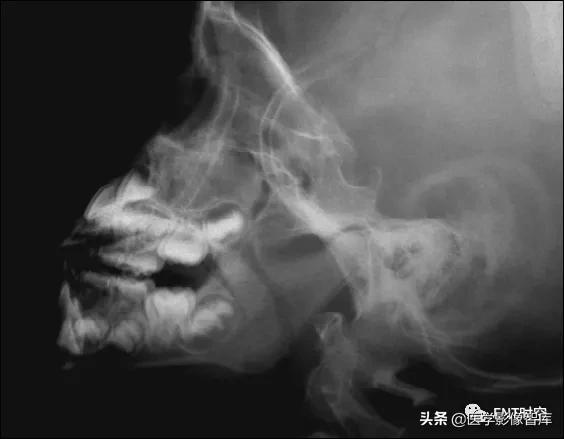

鼻咽侧位片的测量方法(三)

腺样体长度的测量

- 使用平行曲线法,沿C3椎体前软组织前缘向上划与颈椎相平行的直线,上行至软腭后下缘,水平转折向前向上划与软腭后上缘平行的弧线至硬腭后部,此线与突入鼻咽腔的腺样体后、前缘相交为b、a两点,ab间距为腺样体长径。

- 临床上应用较少。

鼻咽侧位片的测量方法(四)

Cohen and Konak法

测量硬腭下1cm处软腭厚度和软腭与腺样体间气

道宽度之比

研究发现比较4种X线平片测量方法中,此方法

与临床内镜观察一致性最强,但应用不多。